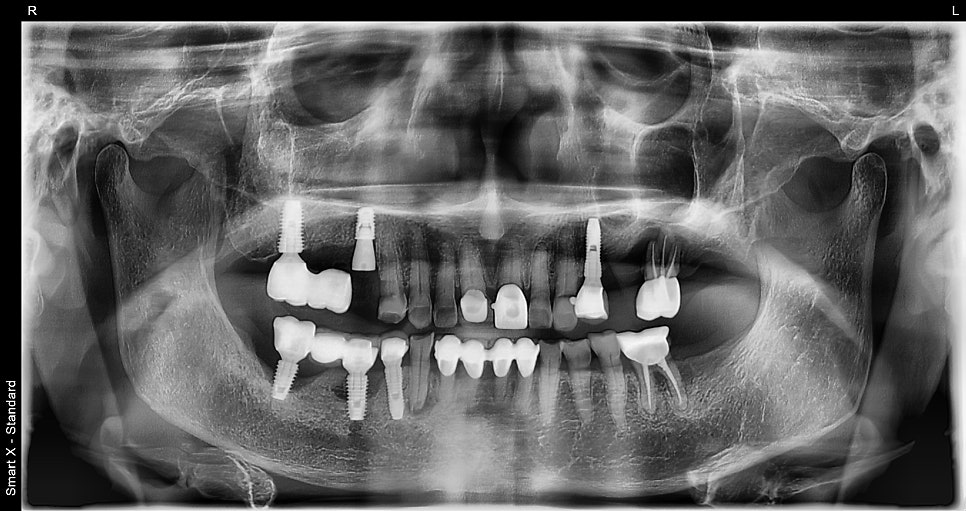

✅ 치료 중 사진

임플란트 수술 직후 파노라마 엑스레이이와 수술 장면입니다.

#15 는 뼈가 다 녹아 발치 후 즉시 임플란트를 식립하고, 기존 #16 임플란트는 제거 했습니니다.

보통 두 번에 나눠 진행하는 수술(식립과 힐링 단추 연결)을

환자분 내원 부담을 줄이기 위해 한 번에 진행했습니다.

처음 내원 시에는 복용약이 많아 출혈 위험이 있어 스케일링과 앞니 크라운 치료만 우선 진행했습니다.

2주 후, 약 복용을 조절하고 전신 컨디션이 안정된 상태에서 1차 수술(식립)과 2차 수술(치유캡 연결)을 한 번에 진행했습니다.

수술은 약 15분 내외로 빠르게 끝났고, 통증이나 부작용 없이 회복되었습니다.